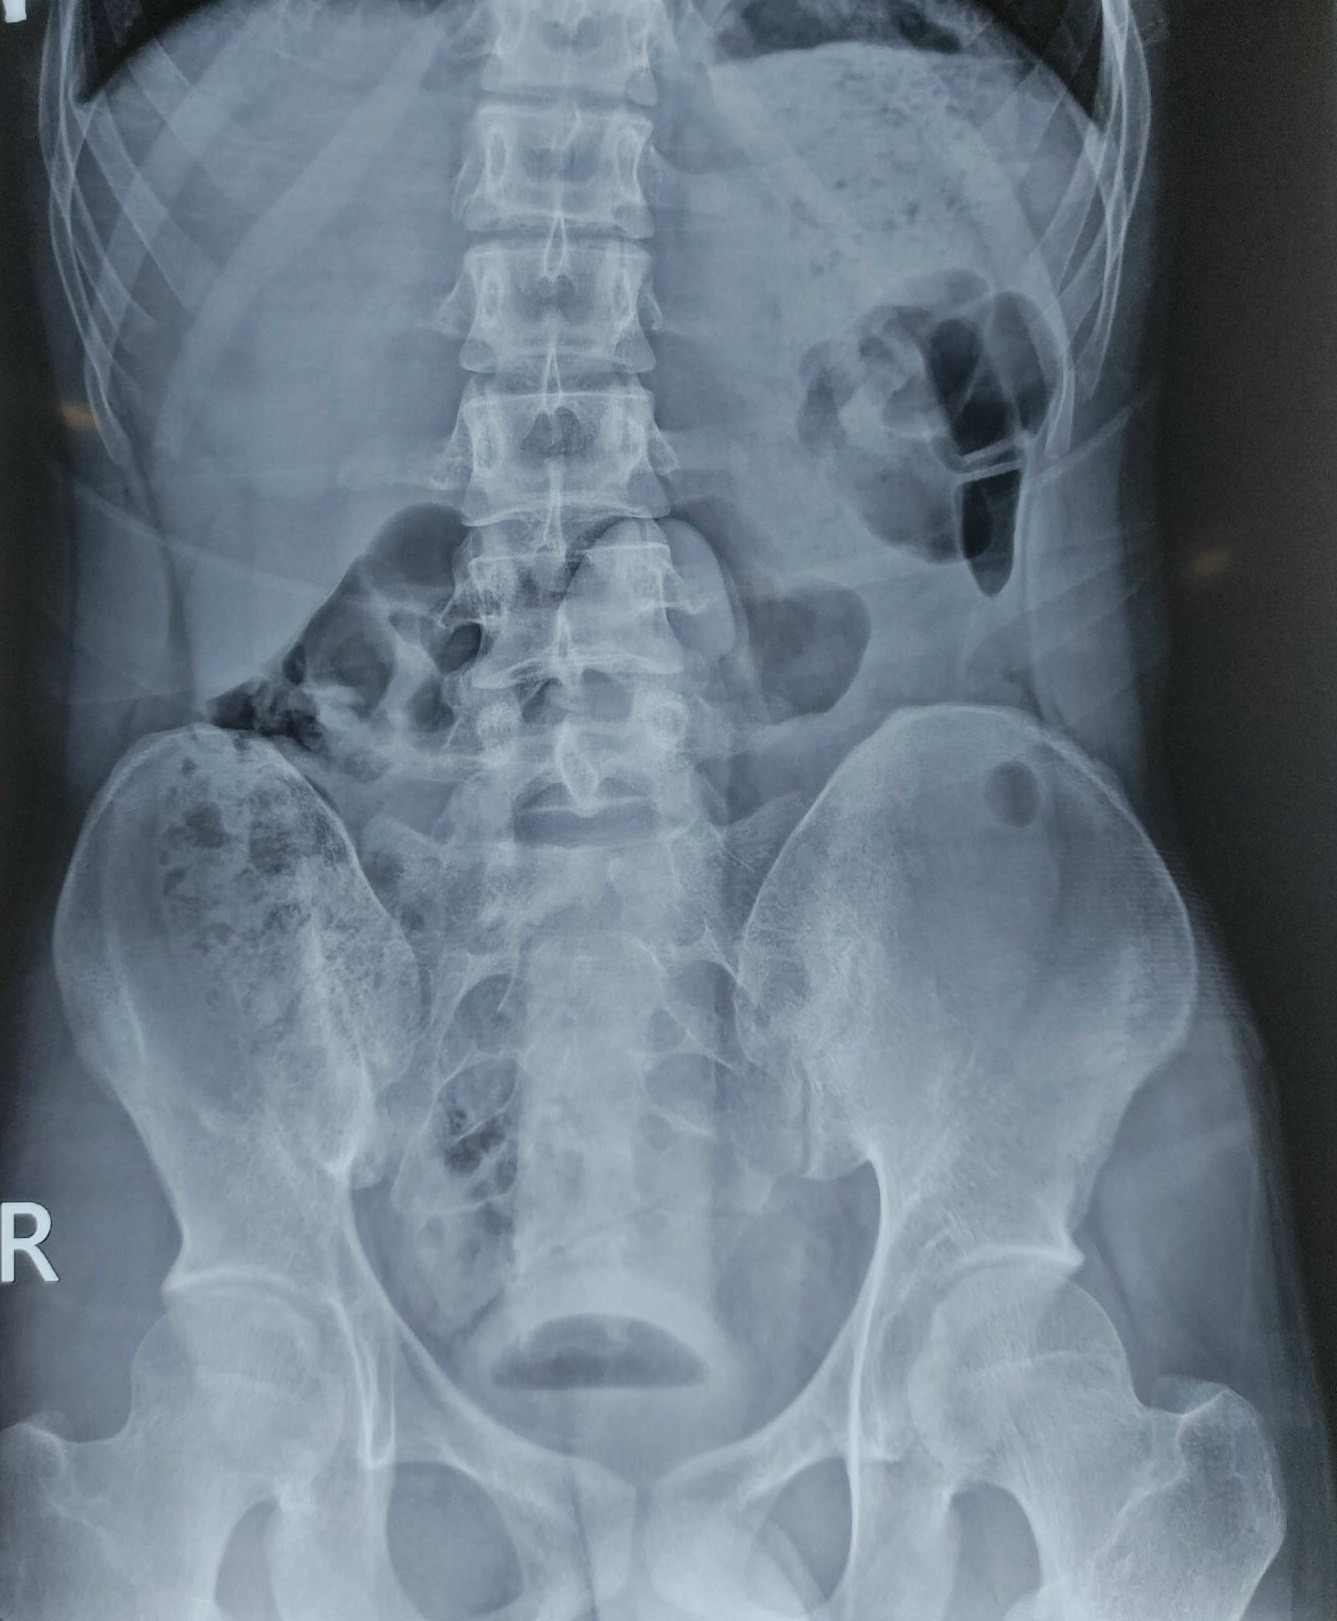

| Hình ảnh X-quang cho thấy dương vật giả nằm trong đường tiêu hóa của người bệnh |

Tại khoa Cấp cứu, sau khi thăm khám và chụp Xquang, các bác sĩ phát hiện trực tràng có dị vật hình dạng giống “dương vật” nằm sâu trong trực tràng nên bệnh nhân được chuyển lên khoa Phẫu thuật - gây mê hồi sức tiến hành lấy dị vật.